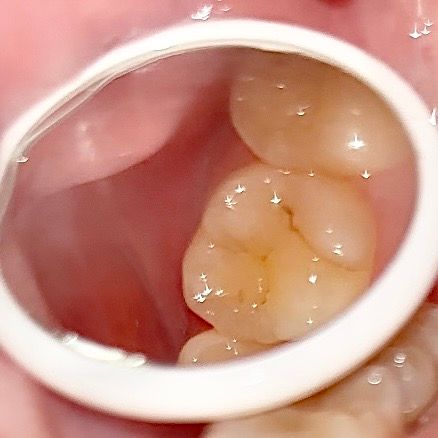

심각한 충치나 치수염 가능성이 있어보이나요??

심각한 충치나 치수염 가능성이 있어보이나요?? 치통인지 아님 생리전증후군인지.. 이쪽 부근에 은은한 통증? 불쾌감이 느껴져서요ㅜㅜ

• 1번 째 사진

치아 파절이 관찰되는데 파절 주위로 크랙이 의심됩니다 충치나 치수염이 아니더라도 크랙으로 통증이 심할 수 있습니다

이정도면 범랑질에 국한된 충치 입니다. 사진이 흐리지만 표면충치로 보이며 당분간 치료 안하고 그냥 지켜보다가 혹시 더 진행되면 충치치료 해도 될 것으로 보입니다.

사진 상으로는 단순 히 착색이 된 정도로 보이며 치수염이나 심한 충치가 의심되진 않습니다.

사진상으로 심각한 충치같이 보이거나 그렇진 않습니다. 간단한 충치치료를하면될것같습니다.